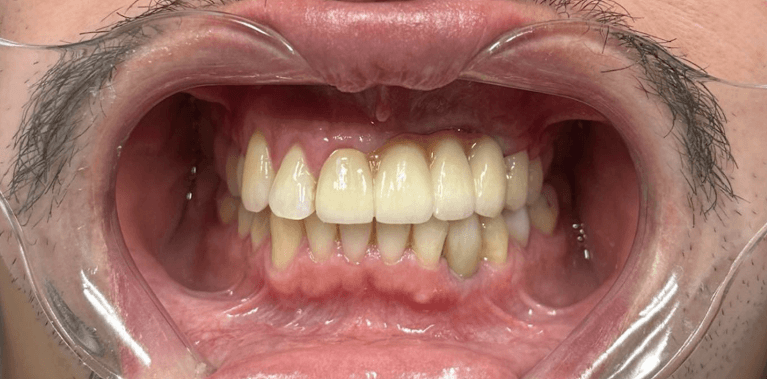

Broken Upper Central incisor with root canal replaced with Immediate implant after extraction.